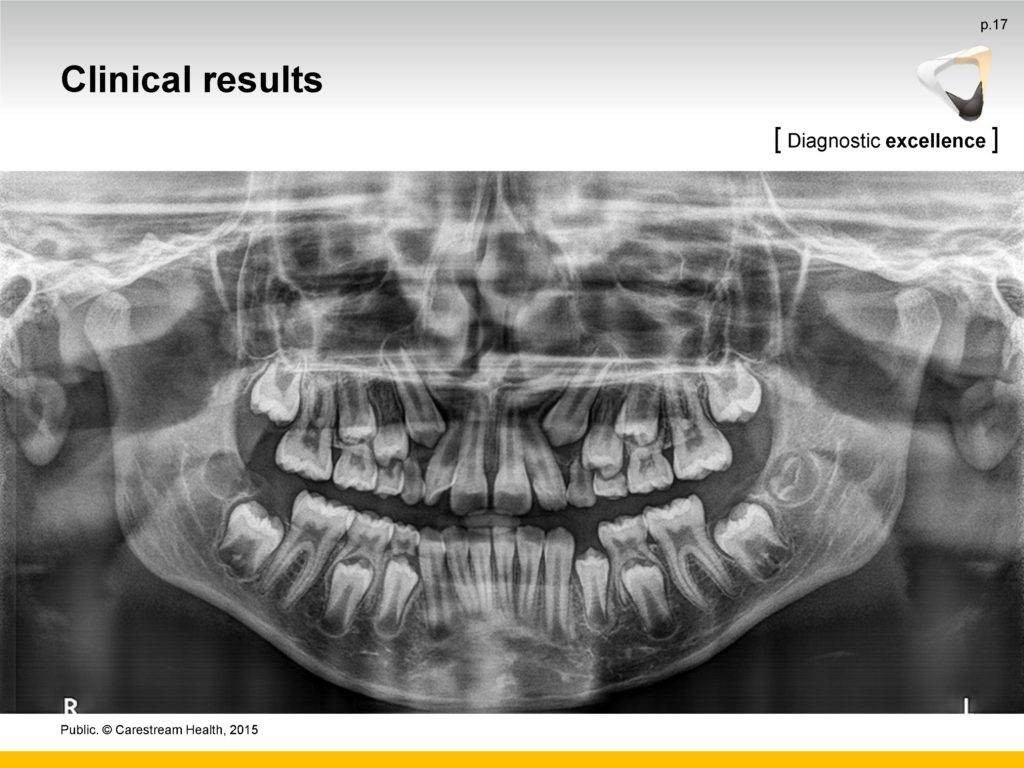

- Uz najnovije algoritme za obradu softvera, CS 8100 minimizira sjene kralježnice i proizvodi jasne, oštre digitalne slike koje su spremne za pregled gotovo odmah.

- Napredni Active Pixel CMOS senzor, sustav za kretanje bez vibracija i 0,5 žarišne točke osiguravaju detaljne, kontrastne, kristalno jasne slike u sekundi

- Snažni filtri bez artefakata povećavaju kontrast i oštrinu jednim klikom